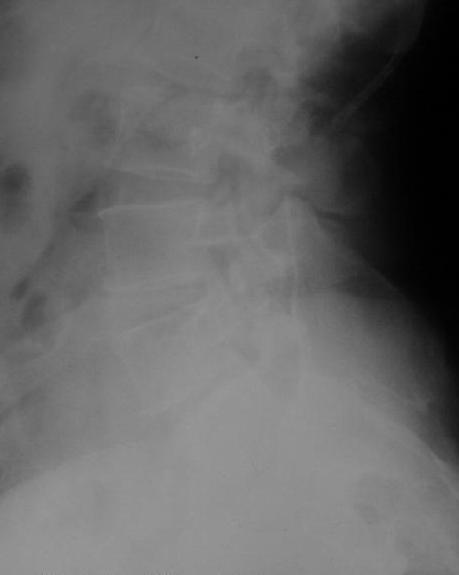

У больной 53 лет в последний год появились сильные боли в пояснице.

Пациентку в первую очередь беспокоят боли в спине, на отсутствие

движений в суставе она вроде и не жалуется. Вопрос насчет тактики.